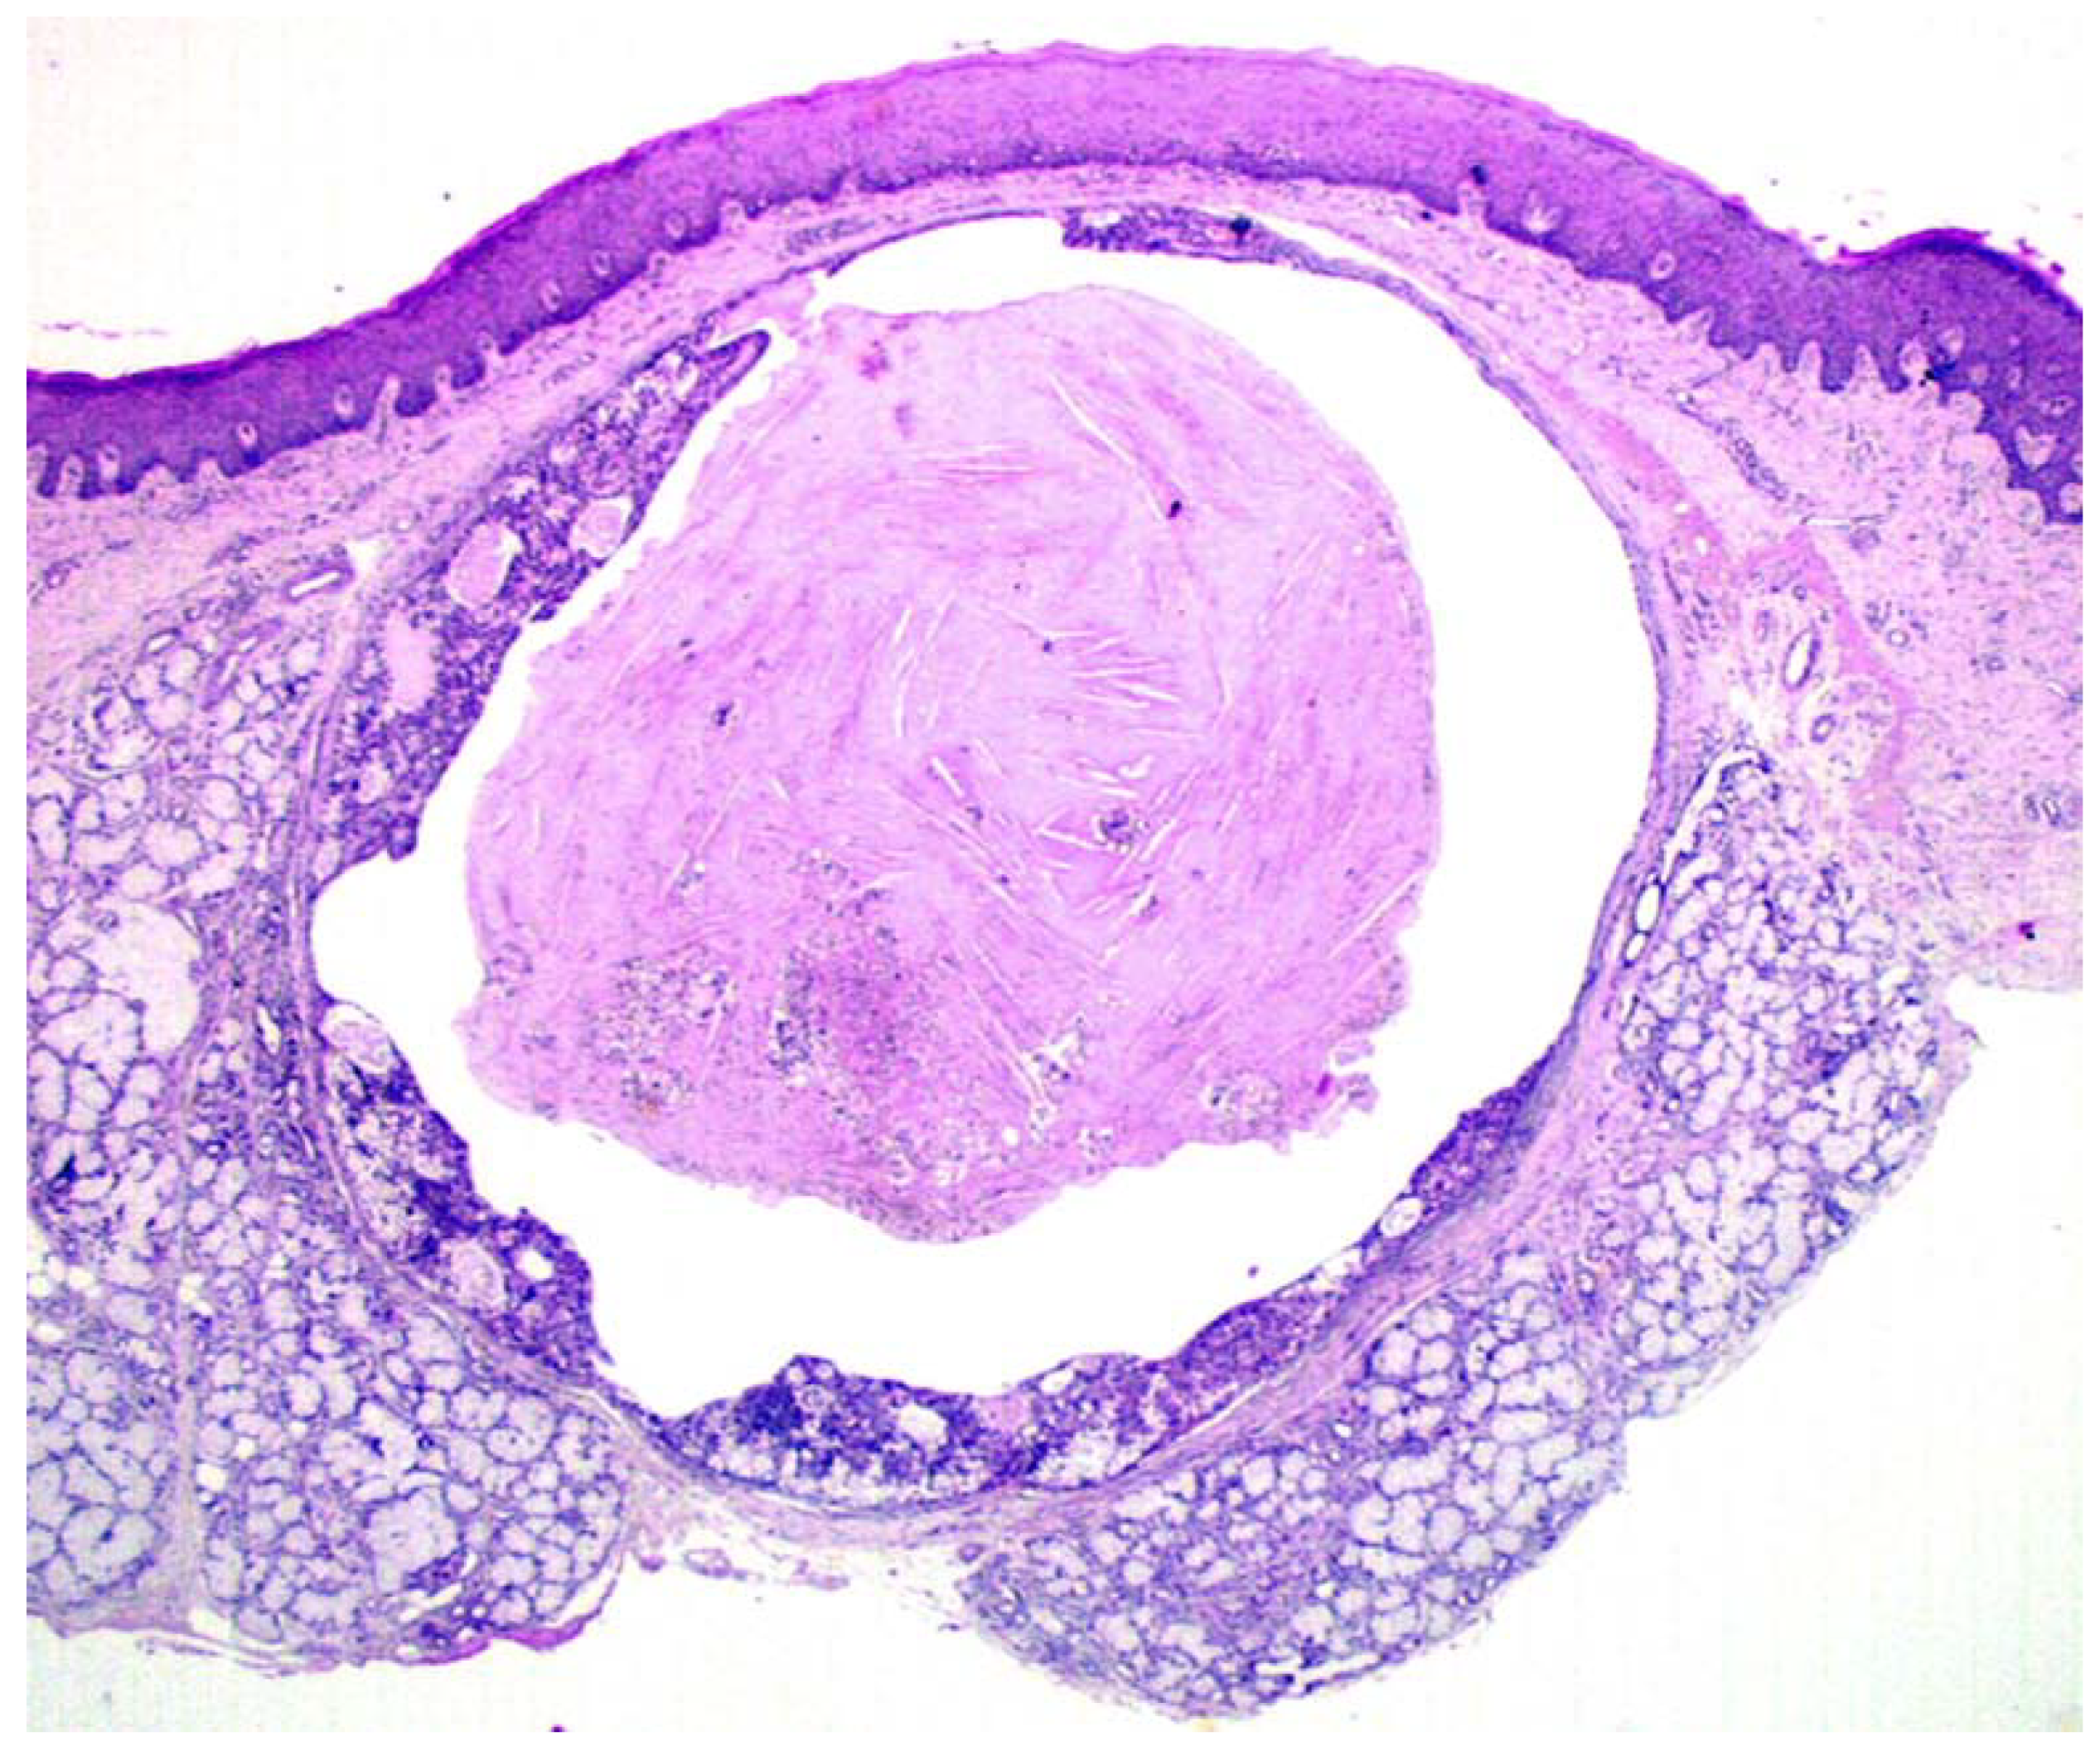

Intra-Cystic (In Situ) Mucoepidermoid Carcinoma: A Clinico-Pathological Study of 14 Cases

Capodiferro, S.; Ingravallo, G.; Limongelli, L.; Mastropasqua, M.G.; Tempesta, A.; Favia, G.; Maiorano, E. Intra-Cystic (In Situ) Mucoepidermoid Carcinoma: A Clinico-Pathological Study of 14 Cases. J. Clin. Med. 2020, 9, 1157. https://doi.org/10.3390/jcm9041157